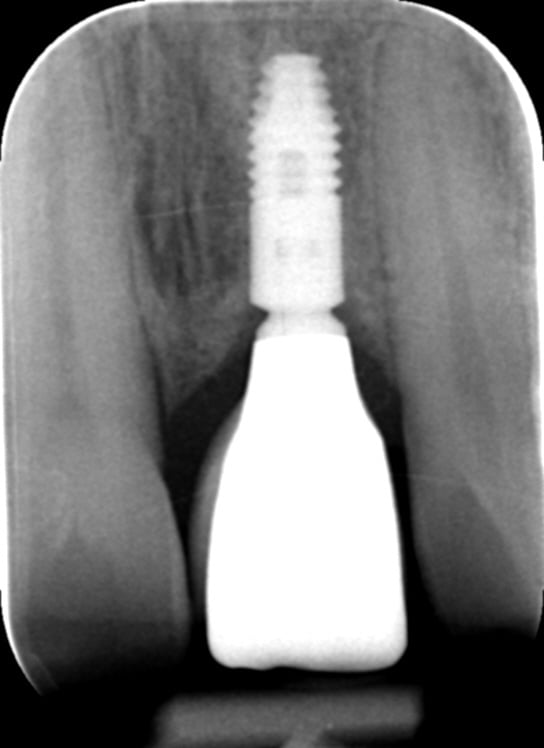

Gallery - Dental Implants

Case 2

Before After